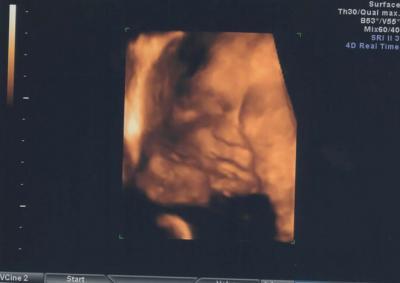

Bild zu

Oh wie süß!!!!!!!! Mein Eumel hat sich heute nur versteckt...hätte ihn doch auch gern mal in 3 oder 4 D gesehen...humpf. GLG Daniela